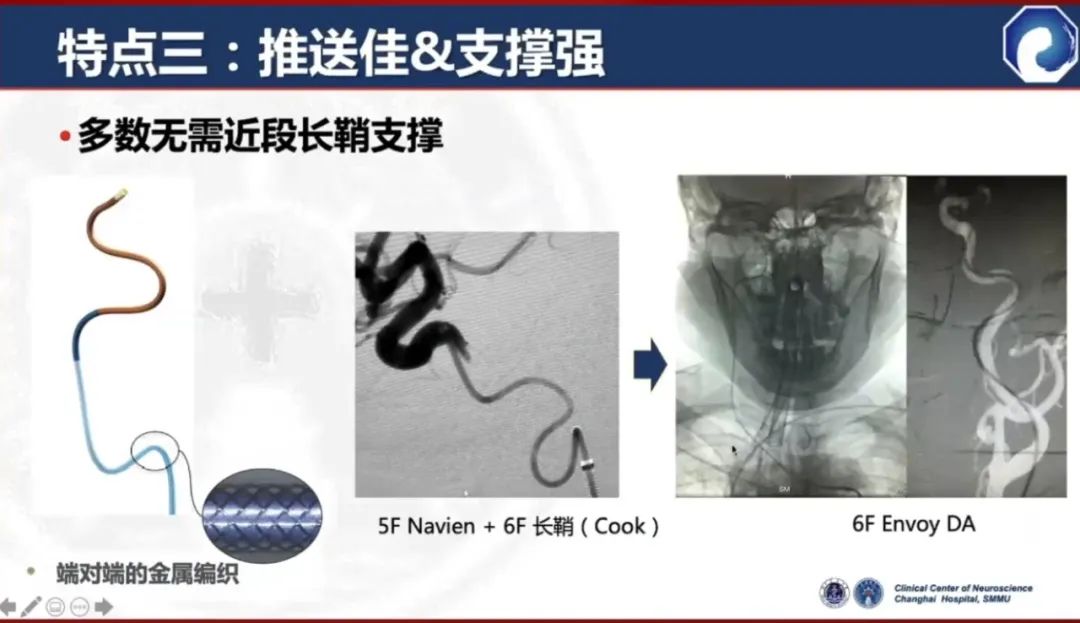

一般情况下,无需长鞘辅助

缺点:对于部分II型弓或比较迂曲的血管,弓部和近端支撑力不足